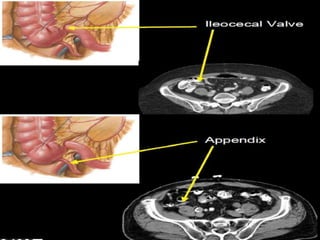

CT cross sectional anatomy.